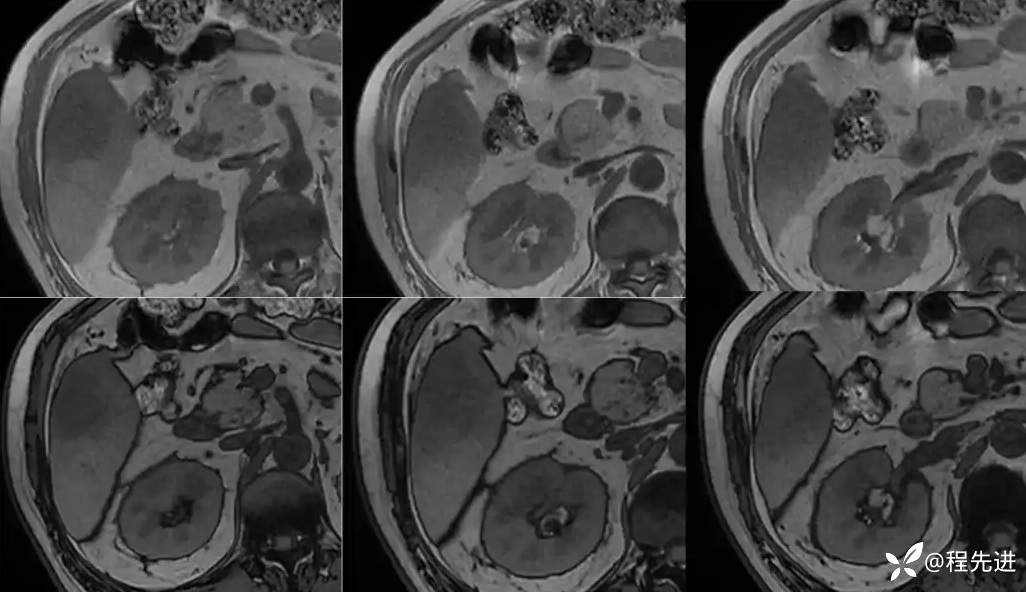

CT平扫:

动脉期:

门静脉期:

门静脉期冠状位:

延迟期: